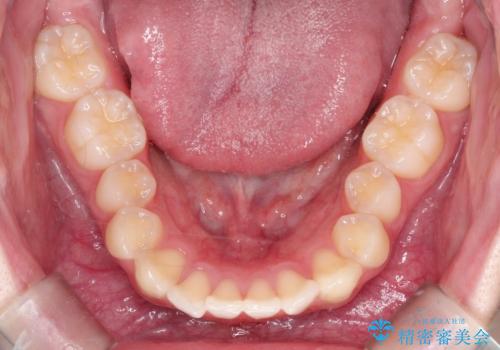

【インビザライン】前歯のガタガタをなおしたい

- 前歯のガタガタを主訴に来院されました。

開咬ぎみであったため、しっかりと前歯が噛むように計画を立てて治療をおこないました。

仕上がりも良く、患者様にも満足していただきました。

インビザラインは前歯を噛ませるような開咬の治療も得意としています。